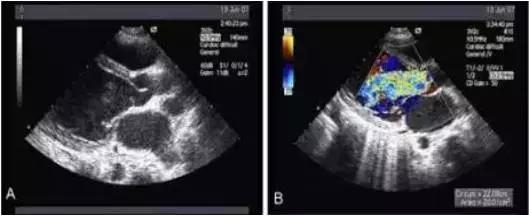

②主动脉夹层在二维超声上表现为病变部位主动脉增宽,其内可见丝裂的内膜反射,该内膜将增宽的主动脉分为真假两腔。

③有时可显示真假两腔相交通之处,表现为撕裂的内膜上有回声中断。假腔中常可显示云雾状回声反射和附壁血栓

夹层病变时真腔中的血流速度快,假腔中的血流速度相对慢。有时还可显示真假腔间相交通的血流,主动脉瘤时增宽的主动脉腔内的血流速度常较慢。此外,位于主动脉根部的主动脉夹层和主动脉瘤,常可显示不同程度的主动脉瓣关闭不全。

在二维超声中可见主动内分离的内膜片呈内膜摆动征,主动脉夹层分离形成主动脉真假双腔征。有时可见心包或胸腔积液。

多普勒超声不仅能检出主动脉夹层分离管壁双重回声之间的异常血流,而且对主动脉夹层的分型、破口定位及主动脉瓣返流的定量分析都具有重要的诊断价值。

应用食管超声心动图。结合实时彩色血流显像技术观察升主动脉夹层分离病变较可靠。对降主动脉夹层也有较高的特异性及敏感性。